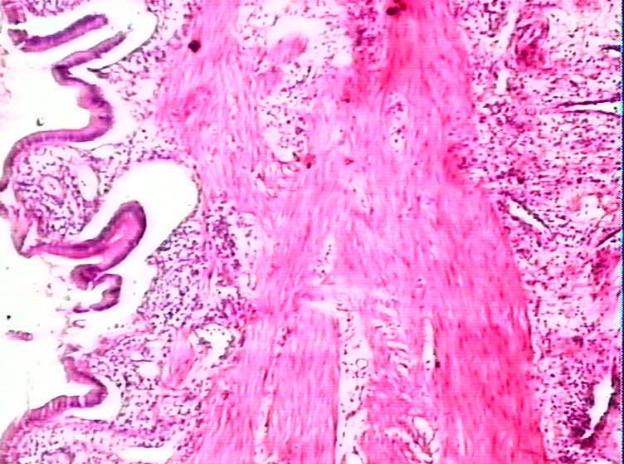

106.关于化脓性炎的叙述,下列不正确的是

表面化脓是指发生在浆膜、黏膜的化脓性炎

黏膜的化脓性炎又可称为脓性卡他

化脓性炎可不伴有坏死

蜂窝织炎是指弥漫性化脓性炎

当脓液在组织间隙或体腔、自然管腔中积聚时称为积脓

正确答案:C